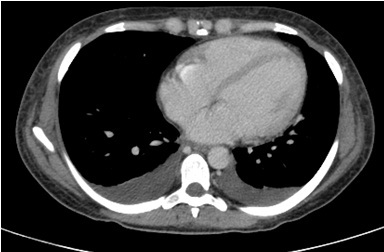

DP

Derrame pleural bilateral.